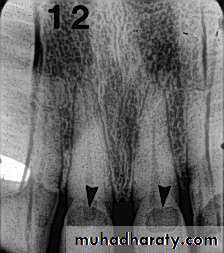

Advanced visual-Fiberoptic transillumination (FOTI)

Transillumination takes advantage of the opacity of a demineralized tooth structure over more translucent healthy structures.The decalcified area will not let light pass through as much as it does in a healthy area, generating a shadow corresponding to decay.

Illumination is delivered by means of fiberoptics from the light source to the tooth surface using a fiberoptic handpiece

• Radiography

Carious lesions are detectable radiographically when there has been enough demineralization to allow it to be differentiate from normalThey are valuable in detecting proximal caries which may go undetected during clinical examination.